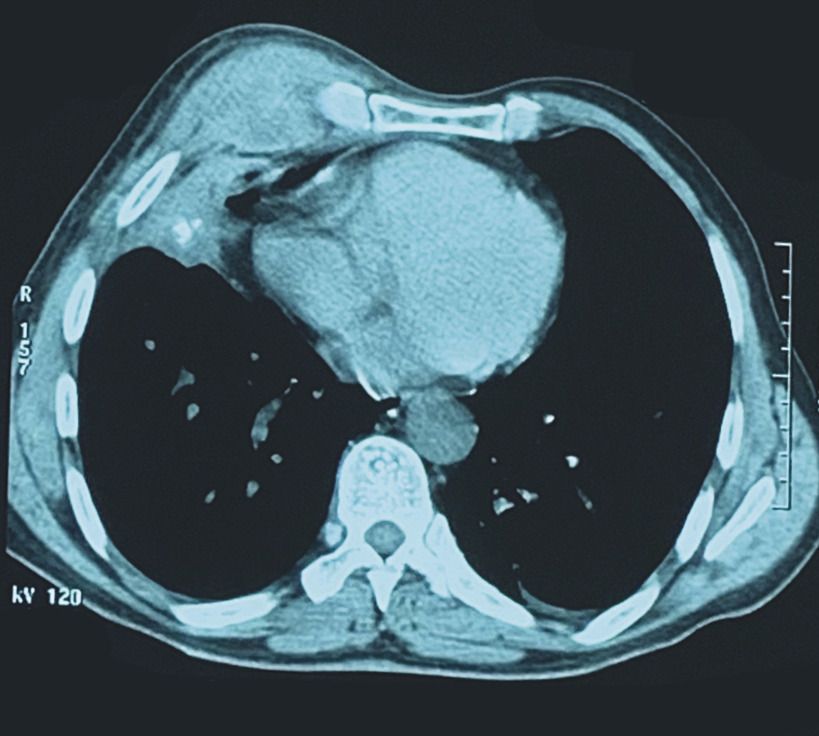

Ce patient de 48 ans, tabagique chronique (25 paquets-années), avait depuis 1 mois une tuméfaction parasternale droite fluctuante en son centre, avec une peau inflammatoire en regard. L’échographie des parties molles montrait une collection hétérogène et hypoéchogène au niveau de la paroi thoracique antérieure droite. La tomodensitométrie thoracique montrait un processus lésionnel pariétal parasternal droit mesurant 68 x 35 x 28 mm en continuité avec un foyer pulmonaire droit (fig. 1 ). Le bilan biologique montrait un syndrome inflammatoire, avec une protéine C-réactive à 56 mg/L, des lymphocytes à 12 500 éléments/mm3 ; la recherche de bacilles de Koch dans les expectorations et dans le liquide de ponction de la collection pariétale était négative à l’examen direct. La biopsie mettait en évidence des granulomes épitélioïdo-giganto-cellulaires avec nécrose caséeuse (fig. 2 ). La sérologie du VIH était négative, et le patient mis sous traitement antituberculeux pendant 6 mois, avec une bonne évolution clinique et radiologique.